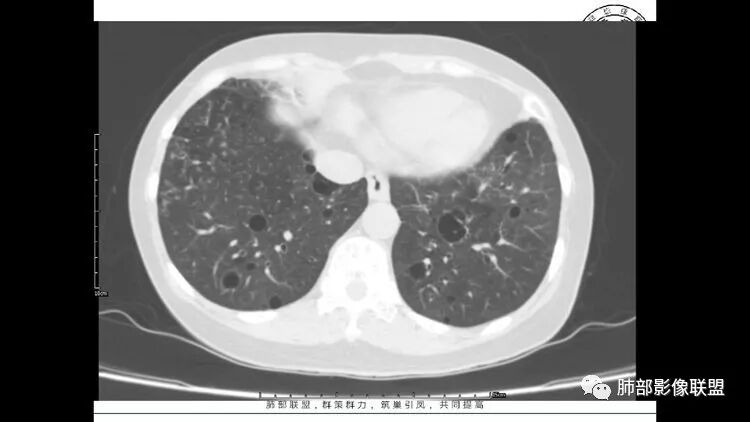

老年女性,眼炎入院,血常规正常,双肺多发囊状影,病变随机分布,形态单一,与血管关系密切,考虑LIP。左下肺混合GGO,边界尚清,贴近囊腔,鉴别腺癌。炎症指标无异常暂不考虑感染性病变。

胸CT:1.双肺多发囊性变,以中下肺为主,病变边缘可见肺动脉,部分囊内可见分隔及肺动脉,双下部分肺野周围可见小叶中心结节及树丫征。

2 左肺上叶尖后段 右肺上叶前段 右肺下叶外基底段 结节影,边界清楚,可见柔软毛刺,左肺下叶后基底段混合密度影。

3.纵隔淋巴结肿大?,以主动脉弓为界向上向下增大。

考虑:淋巴瘤肺浸润,眼部症状考虑与此有关;LIP?;继续鉴别肺腺癌?血管炎?。

双肺多发磨玻璃结节,其内可见空腔,周围边界清晰,多发囊,左肺实性结节。考虑间质性肺炎,LIP可能性大。鉴别腺癌。

患者中年女性,因右眼红痛1天就诊。胸CT:双肺多发囊性变及结节影,囊以中下肺为多,部分囊内可见分隔及肺动脉,结节部分为实性,部分为混合性,边缘光滑,未见明显毛刺、棘突、胸膜牵拉及血管集束征象。双中下可见支气管扩张及树丫征。淋巴结无明显肿大。综合考虑:一元淋巴细胞间质性肺炎。多元鉴别肺腺癌并转移等恶性病变。

LIP影像重要线索一句话:

双肺下叶分布为主的间质改变(磨玻璃影、小叶间隔增厚)、散在气囊影(常有血管贴边)、边界不清小结节